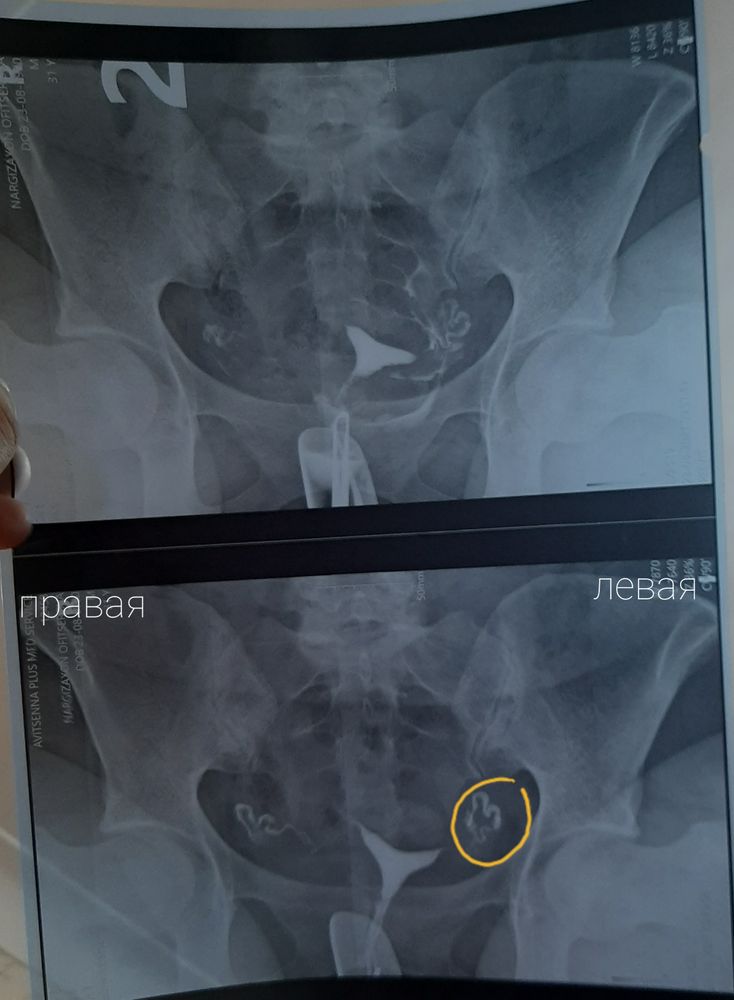

Изображение На первом снимке я обвела кружочком участок. Это ампулярный отдел,т.е. труба или контраст? Просто справа на верхнем рисунке контраст весь рассеялся, а на левом будто бы слабо, может это вообще труба, если это так то она плохо проходима? Вроде рассеянный дым есть везде, и слева и справа. Или я просто уже зациклилась

Изображение